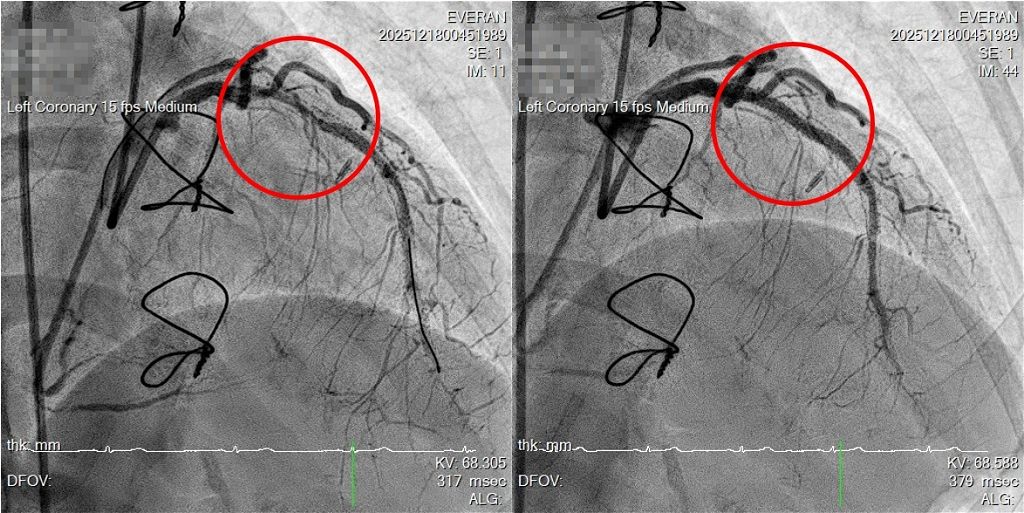

57 歲的李小姐長期罹患冠狀動脈疾病,曾在醫學中心接受心導管治療並放置藥物塗層支架,後續又因病灶進展再接受冠狀動脈繞道手術。然而術後胸悶與放射性背痛症狀仍反覆出現,近期明顯加劇,經長安醫院心血管中心主任盧炯睿醫師檢查,發現手術繞道血管已發生阻塞,支架治療的冠狀動脈也出現嚴重支架內再狹窄,並合併高度鈣化,使血流供應受限。盧醫師最終以「IVL血管內震波碎石術」震碎鈣化組織,順利置放藥物支架,終結了困擾患者多年的「心頭之患」。

回顧病史,李小姐多年前即接受過冠狀動脈藥物支架治療,四年前因再次狹窄於他院接受心導管介入,惟效果有限,最終改以外科繞道手術處理。未料繞道血管後續仍發生阻塞,使心臟灌流再度仰賴原本已高度病變的冠狀動脈,形成結構複雜且風險較高的臨床情境。

面對此一挑戰,盧炯睿醫師指出:「評估患者多次介入治療後仍反覆狹窄,且合併嚴重鈣化的支架內再狹窄病灶,若僅使用傳統高壓球囊,容易出現擴張不足,甚至增加血管剝離或破裂的風險,因此需依血管結構特性選擇更合適的治療方式。」在完整評估患者病史與血管條件後,醫療團隊選擇導入「IVL 血管內震波碎石術」。

該技術透過低能量、精準控制的震波作用於血管壁內鈣化組織,破壞深層鈣化結構,使血管恢復順應性,進而協助後續支架的擴張與置放。盧炯睿醫師進一步說明,IVL 的概念可比喻為「處理老舊水管內頑固水垢」,不同於單純以高壓球囊硬撐,IVL 著重於改變鈣化結構本身,以降低血管損傷風險並提升治療效果。但該技術並非適用於所有病人,仍需依個別病灶條件審慎評估。